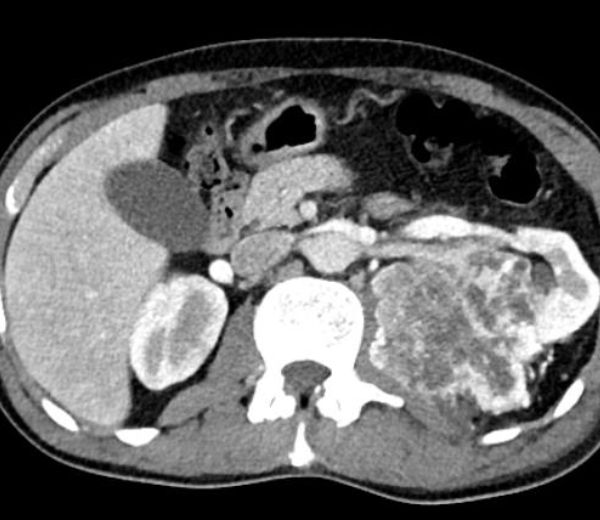

Muž 45 let – potíže s mikcí

Jste lékař urolog a přichází k vám pacient odeslán od praktického lékaře (PL). PL k Vám odesílá muže ve věku 45 let, pro nespecifické mikční potíže, které se objevily po prochlazení. Krev v moči pacient nepozoroval, lékařem to však nebylo došetřeno. Pacient nebyl doposud urologicky sledován, neléčil se.